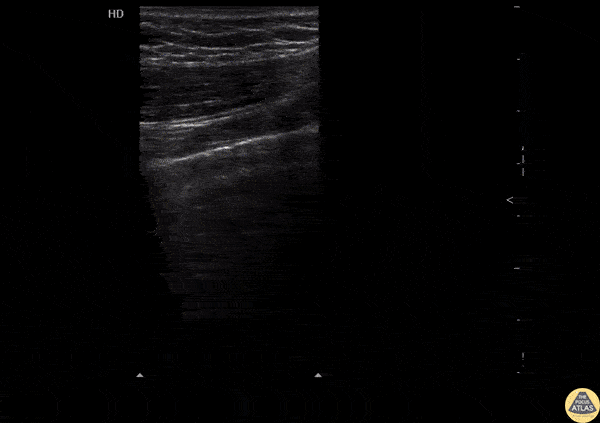

Pulmonary - Normal Lung Sliding

Normal lung sliding with regular appearing pleural lining. Image courtesy of Robert Jones DO, FACEP @RJonesSonoEM Director, Emergency Ultrasound; MetroHealth Medical Center; Professor, Case Western Reserve Medical School, Cleveland, OH View his original post here